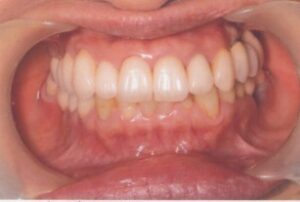

- 10年前から他の歯科医院にて部分的な治療を受けたが、見た目が良くない・噛めないとのことで再治療を希望された。アングルクラスⅠであった。左上奥歯がない。

- 上顎左側にインプラントを3本し、

- オールセラミック4本にて被せ物を行なった。

- 審美的な仕上がりで、患者自身も満足した。23年経過し良好である。

現在は2〜3ヶ月おきのメインテナンス中である。